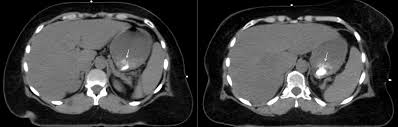

What Does Breast Cancer Look Like On A Ct Scan / Breast Cancer Radiation Planning Imaging Technology News - High risk of breast cancer.. Learn the stage of your cancer. Your doctor may recommend a breast mri scan if you have a diagnosis of breast cancer to determine the extent of the cancer. At left is a ct scan, while the center image is from a pet scanner. If your doctor suspects that you have cancer near your abdomen, they may recommend an abdomen ct scan. Ct, mri, and pet scans can also tell if your cancer spread.

Finding breast lumps and seeing change in the size and shape. Ct scans can help doctors: This test is most often used to look at the chest and/or belly (abdomen) to see if breast cancer has spread to other organs. Leak or rupture of a breast implant. With cancer cells, they appear as bright spots due to its higher metabolic rate compared to normal cells. A ct scan is a safe test for most people but like all medical tests it has some possible risks. As you probably know, a ct scan is one of several imaging techniques—this one primarily for looking at organs. Ct scans can be misread or misinterpreted. This helps radiologists identify areas where cells are suspiciously active, which can indicate cancer. As other answers have stated, what ct (and mri, and ultrasound) can show is the overall size of the lymph nodes, and in some cases how much blood supply they have. They may also use it to learn more about the cancer after they find it. Pet scan for breast cancer. If you have a condition like cancer, heart disease, emphysema, or liver masses, ct scans can spot it or help doctors see any changes.

Imaging and lobular breast cancer. When a breast cancer has been diagnosed, some people have a ct scan of their chest and tummy (abdomen) to stage the breast cancer. 4.9k views reviewed >2 years ago What does breast cancer look like? Your doctor and radiographer make sure the benefits of having the test outweigh these risks. Controversy continues to surround the question of whether ct and bone scans should be standard in evaluating patients for these metastases, or whether integrated pet/ct scanning might. To help you prepare, here's a look at what to expect. With cancer cells, they appear as bright spots due to its higher metabolic rate compared to normal cells. It is common for patients to receive a diagnosis for cancer of unknown primary. Ct scans can be misread or misinterpreted. The big problem with imaging is that we know, with certainty, that we can't usually. Combining a pet scan with an mri or ct scan can help make the images easier to interpret. As you probably know, a ct scan is one of several imaging techniques—this one primarily for looking at organs.

This tracer can help identify areas of cancer that an mri or ct scan may not show. However, they are also scanning my thorax. A ct scan can be wrong: We'll show you breast cancer pictures to help you identify any physical traits of the condition. Areas of tumor tend to pick up the labeled compound and show up as foci of increased activity either bright or dark spots depending how the image is displayed. My bone mets were discovered during a bone scan (i.e. If your doctor suspects that you have cancer near your abdomen, they may recommend an abdomen ct scan. Although breast pet scans use radioactive material, the dose of radiation given to the patient is very minimal. Ct scans can show a tumor's shape, size, and location. Identify the correct area for. Nuclear) and show up on my ct scans as well. Amongst everything that's been going on i have not been checking my breasts, stupidly i was looking for cancer in other areas and now i think my breast may be the culprit. Ct scans can produce false negatives and false positives.